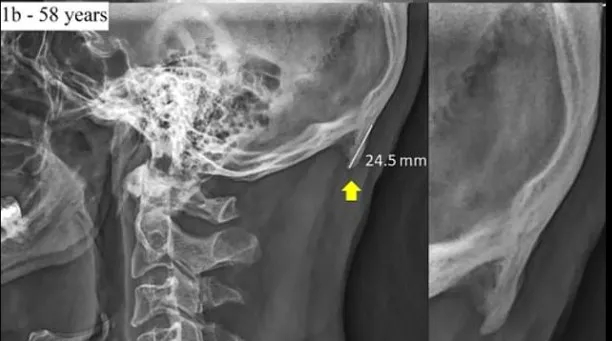

Cụ thể, trường Đại học Sunshine Coast, Queensland, Úc mới đây đã công bố các hình ảnh chụp x-quang, chứng minh phần xương chẩm của hộp sọ con người có xu hướng phát triển nhiều hơn, do họ cúi đầu quá lâu lúc dùng điện thoại hay máy tính.

Hộp sọ của một người 58 tuổi có phần xương chẩm bình thường